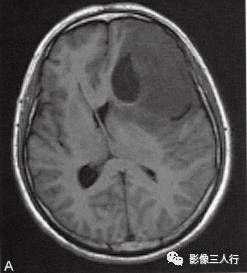

左侧额颞叶多形性胶质母细胞瘤

A.T1WI横断面;B.T2WI横断面;CFLAIR横断面;D.T1WI增强;E.T1WI增强冠状面;F.T1WI增强矢状面;G.HE×40;H.GFAR( )×40

影像学表现:

左侧额颞叶见较大不规则囊实性肿块,大小约5.4cm×8.3cm,平扫T1WI呈低信号、T2WI呈高信号(图A、B),肿块内有斑片状囊变区;增强扫描肿块实性部分呈不均匀明显强化,囊性部分呈环形强化(图D~F)。肿块占位效应明显,周围见环形水肿(图C)。